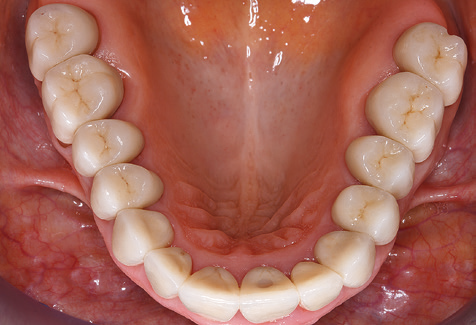

Eine 52-jährige Patientin stellte sich nach Zahnverlust im 3. Quadranten erstmals 2004 vor. Sie hatte den Wunsch nach einer prothetischen Neuversorgung. Im Rahmen der parodontologischen und radiologischen Diagnostik zeigte sich ein ausgeprägter parodontologischer Behandlungsbedarf. Die Zähne 48, 28, 27 zeigten zudem eine infauste Prognose und wurden entfernt (Abb. 1). Nach der erfolgreich abgeschlossenen systematischen PARTherapie wurde eine festsitzende implantatprothetische Versorgung mit Insertion von fünf Implantaten in Regio 35, 36, 37 und 46, 47 durchgeführt. Die prothetische Versorgung der natürlichen Zähne erfolgte mit verblendeten Zirkonoxidkeramikkronen, die Implantate wurden mit zweiteiligen individuellen Zirkonoxidabutments und ebenfalls verblendeten Kronen aus einer Zirkonoxidkeramik versorgt (Cercon base colored, Dentsply Sirona Lab). Die definitive Insertion der prothetischen Versorgung erfolgte im Jahr 2005.

Aufgrund der bestehenden parodontalen Vorerkrankung erfolgte die unterstützende Parodontaltherapie (UPT) in den ersten Jahren in einem DreiMonatsIntervall. Dabei zeigte die Patientin eine hohe Motivation und gute Compliance. Bei den jährlich erhobenen Sondierungsbefunden zeigten sich stabile parodontale Verhältnisse mit einem BOPIndex unter fünf Prozent. Aufgrund der stabilen parodontalen Situation und der guten Mitarbeit der Patientin wurde ab dem sechsten Jahr der prothetischen Funktionsphase das Recallintervall auf halbjährlich umgestellt. Auch mit diesem veränderten Recallintervall zeigten sich bei der jeweils jährlichen Aufnahme des Parodontalstatus stabile parodontale Verhältnisse, ohne Zunahme der Sondierungstiefen und einem BOPIndex unter fünf Prozent (Abb. 2a und b).

Im Rahmen der ZehnJahresKontrolle zeigten sich keine Hinweise auf einen fortschreitenden parodontalen Attachmentverlust oder einen periimplantären Knochenverlust (Abb. 3).

Die Patientin befindet sich weiterhin in einem halbjährlichen Intervall für die UIT. Nachfolgend werden am Beispiel dieser Patientin die einzelnen Arbeitsschritte einer strukturierten UPTSitzung aufgezeigt, so wie sie nahezu unverändert über den gesamten Funktionszeitraum von immerhin zwölf Jahren durchgeführt wurden. Natürlich wurden über diesen Zeitraum einige neue Materialien und Geräte in das Konzept integriert. In diesem klinischen Fallbericht wird das aktuelle Material und Gerätekonzept präsentiert.

Für den klinischen Langzeiterfolg des parodontal kompromittierten Patienten ist die standardisierte und regelmäßige risikoadaptierte Betreuung im Rahmen der UPT der zentrale Baustein des Behandlungserfolgs. Dies gilt in besonderer Weise für Patienten, die nach erfolgreich abgeschlossener parodontaler Sanierung mit Implantaten versorgt wurden (Abb. 11a und b).